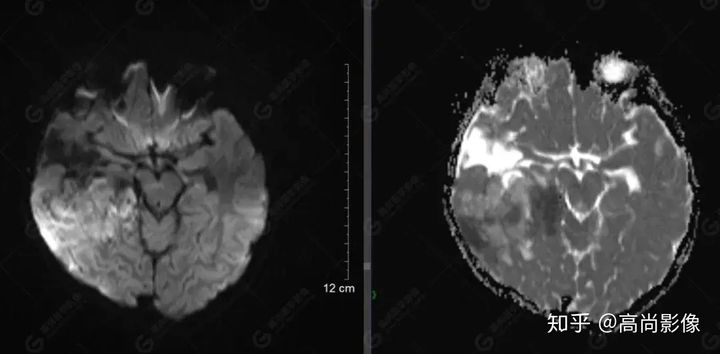

右側(cè)顳葉腫瘤切除術(shù)后(具體不詳):右側(cè)顳部骨質(zhì)不連續(xù)呈術(shù)后改變,右側(cè)顳葉術(shù)區(qū)見片狀長T1長T2信號影,F(xiàn)LAIR呈低信號;術(shù)區(qū)后方右側(cè)顳枕葉見一巨大占位性病變影,邊界欠清,大小約6.2×5.8×4.3cm(前后×左右×上下),信號不均勻,T1WI呈等稍低信號間雜少許高信號,T2WI呈高稍低混雜信號,DWI示部分病灶彌散受限,相應(yīng)ADC圖減低,磁敏感序列見部分呈極低信號,增強(qiáng)掃描可見明顯不均勻強(qiáng)化,鄰近硬腦膜及小腦幕增厚并明顯強(qiáng)化;另延髓右前方及右側(cè)橋小腦角區(qū)見一不規(guī)則形異常信號影,大小約3.2×1.3×3.7cm(左右×前后×上下),呈長T1稍長T2信號,F(xiàn)LAIR呈等信號,DWI未見受限,增強(qiáng)后明顯均勻強(qiáng)化,鄰近腦膜明顯強(qiáng)化。鄰近腦實質(zhì)及右側(cè)顳角明顯受壓;左側(cè)大腦半球未見局灶性信號異常,中線結(jié)構(gòu)稍左移。